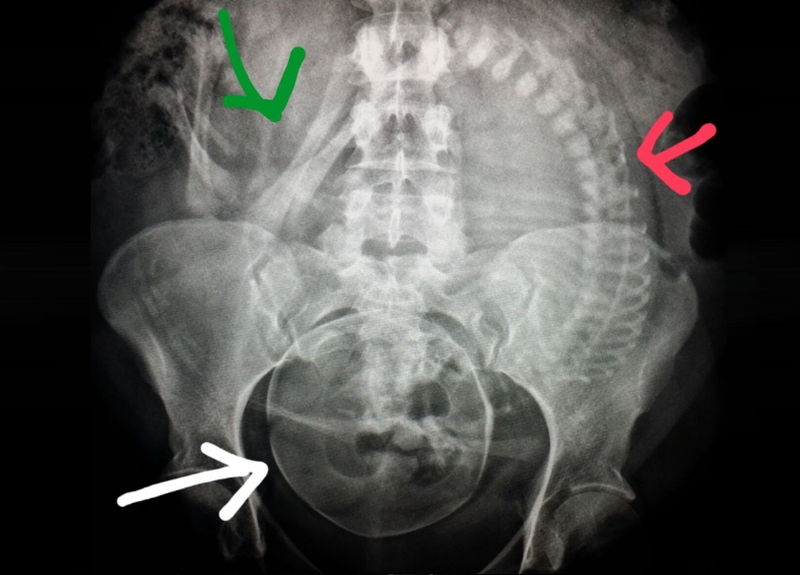

Tia X là một loại tia bức xạ, có thể đi qua các mô mềm và tế bào trong cơ thể. Loại tia này dễ dàng xuyên qua các tế bào, mô mềm hay chất lỏng nhưng lại bị cản bởi các mô đặc như xương. Màu ảnh sau khi chụp X-quang có sự khác nhau chủ yếu vì lý do này.

Các bộ phận như xương, sụn và khớp sẽ được thể hiện thành màu trắng trên phim X-quang. Ngược lại, các phần mềm như tim, phổi, mạch máu sẽ thể hiện ra màu đen. Mức độ đen đậm hay nhạt phụ thuộc vào việc tia X xuyên qua mô ở bộ phận đó nhiều hay ít. Khi tia X xuyên qua càng nhiều thì sẽ cho màu ảnh càng đậm.

Không chỉ liên quan đến từng giai đoạn của thai kỳ mà việc chụp X-quang có ảnh hưởng đến thai nhi không còn phụ thuộc vào liều lượng và vị trí chụp. Dưới đây là bảng phân tích mức độ ảnh hưởng đến em bé tính theo liều lượng tia X mỗi lần cùng vị trí và số lần chụp:

Vị trí chụp | Khả năng hấp thụ mỗi lần chụp | Mẹ chụp bao nhiêu lần mới bị ảnh hưởng (liều 5 rad)? |

Đầu | 0,004 | 1.250 |

Răng | 0,0001 | 50.000 |

Cột sống cổ | 0,002 | 2.500 |

Tay, chân | 0,001 | 5.000 |

Ngực | 0,00007 | 71.429 |

Vú | 0,02 | 250 |

Bụng | 0,245 | 20 |

Cột sống, thắt lưng | 0,359 | 13 |

Khung chậu | 0,04 | 125 |

Vậy bà bầu vào phòng chụp X-quang có sao không? Nếu khi mang thai, mẹ chỉ chụp X-quang một lần thì không gây hại cho thai nhi. Khi liều tia X nhỏ hơn 5 rad cũng không làm tăng nguy cơ ảnh hưởng đến thai nhi. Lý do là bởi liều tia có thể gây dị tật cho thai nhi lên đến trên 15 rad. Vì vậy, phụ nữ khi mang thai vẫn cần khám thai định kỳ để kiểm tra sức khỏe và tầm soát những bất thường (nếu có) khi mang thai.